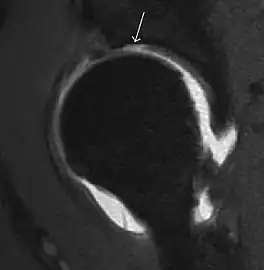

Synovial chondromatosis can be confidently diagnosed by X-ray when calcified cartilaginous chondromas are seen. However, other synovial proliferative processes, such as pigmented villonodular synovitis, require MRI for accurate diagnosis, although noncalcified synovitis can be suspected in radiographs by indirect signs, such as soft tissue swelling and/or erosions in the femoral head, femoral neck, or acetabulum (Figure 7).[1]

Figure 7:

-

Axial CT image of pigmented villonodular synovitis eroding the posterior cortex of the femoral neck.[1] -

Sagittal T2* gradient echo image showing a posterior soft tissue mass with hypointense areas secondary to hemosiderin deposition.[1] -

In synovial proliferative disorders, MRI demonstrates synovial hypertrophy. In the case of PVNS, characteristic foci of low signal intensity related to hemosiderin deposition are better seen on gradient echo T2* images (Figure 7). In the case of synovial osteochondromatosis, the synovial hypertrophy is accompanied by intermediate signal cartilaginous loose bodies and/or low signal calcified loose bodies.[1]